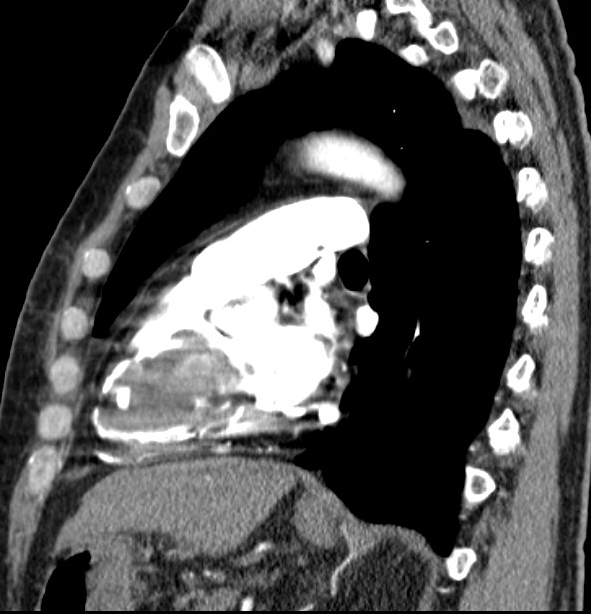

An electrocardiogram showed normal sinus rhythm with nonspecific T-wave changes. His blood pressure was normal. Initial blood work showed mild hyperbilirubinemia, thrombocytopenia, elevated BNP and D-dimer. A CT angiogram of pulmonary artery showed a 7.5 x 4.6 cm mass arising from the right ventricle (RV). A transthoracic echocardiogram (TTE) showed right atrial (RA) and RV dilation with a large mobile heterogeneous mass taking up most of the ventricular cavity and prolapsing into the right atrium during systole, obstructing flow through the tricuspid valve with 45% of Left ventricular ejection fraction (LVEF). A cardiac MRI confirmed heterogenous RV mass with late gadolinium enhancement, attached to inferior wall of the RV causing significant compromisation RV function.